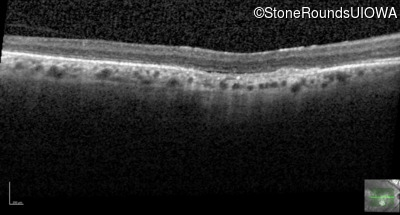

Optical Coherence Tomography - Left - 20/80

Exemplar / OCT Stack

Infrared Fundus Photograph - Right - 20/125 -2